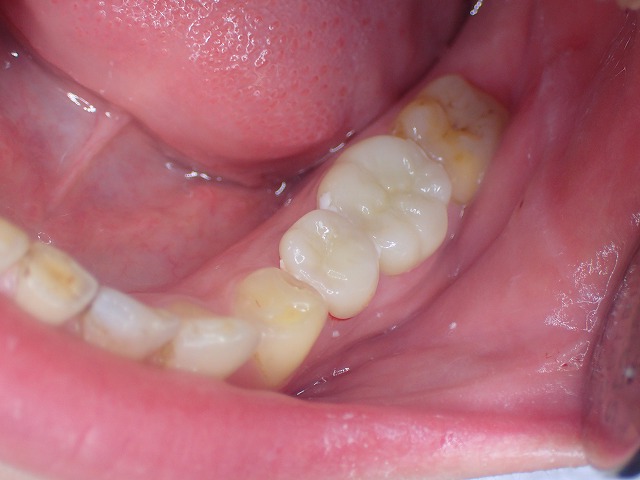

右下

同じくコンタクトしていません。

cad/cam冠はすぐに減るので

両側の摩耗したCAD/CAM冠を

ジルコニアクラウンに交換できました。